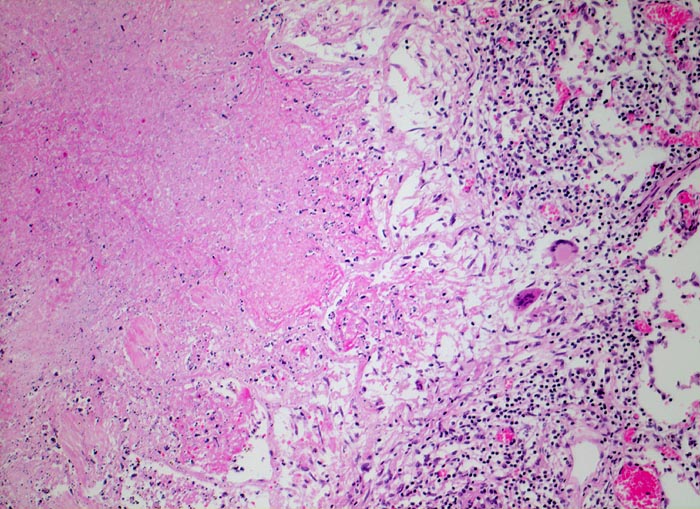

• Tuberkulöse Herde ausgehend von vollständig oder partiell entzündlich zerstörten Bronchiolen in unmittelbarer Nachbarschaft von Arterien.

• Granulome mit zentraler käsiger Nekrose mit Kerntrümmern umgeben von einem Epitheloidzellwall und einem äusseren blauen Saum von Lymphozyten.

• Schlanke spindelige Epitheloidzellen und einzelne Riesenzellen vom Langhanstyp mit peripher hufeisenförmig angeordneten Kernen.